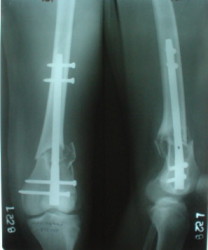

This is great. I would never have thought of doing antegrade nailng for such a #. I would also have never dreamt of such range of flexion.

This is not best flexion reached after the injury/surgery. The patient was obese and negative to physical activity.

The mobilisation of knee is started immediately from the second day. Weight bearing is permitted as in any other interlocked nailing. That is, Toe touch to start with and within four days, partial to in another two weeks, full weight bearing. Of course that is assuming that the correct size nail has been used. Up to 70 kg body weight, 11no will be good enough and 12mm if more.Usually at the 1st followup, at 6 weeks time, they have full flexion..I

have seen a few surgeons putting in a drain, but I have not found it unnecessary. There has never been any effusion needing active treatment.

Enclosing a recent intraop picture